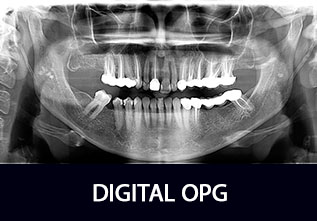

DIGITAL OPG

An OPG (Orthopantomagram) is a panoramic scanning dental X-ray of the upper and lower jaw. It shows a flattened two-dimensional view of a half-circle from ear to ear. Panoramic x-rays allow images of multiple angles to be taken to make up the composite panoramic image, where the maxilla (upper jaw) and mandible (lower jaw) are in the viewed area.

An OPG also demonstrates the number, position and growth of all the teeth including those that have not yet erupted through the gum. It is different from the small close up x-rays dentists take of individual teeth. It shows less fine detail, but a much broader area of view. This can be particularly useful to check hard to see areas like wisdom teeth, or the development of a child’s jaw and teeth, useful for assessing for development generally, but also orthodontic need. It is also often used to check your jaw joint, called the TMJ (temperomandibular joint)